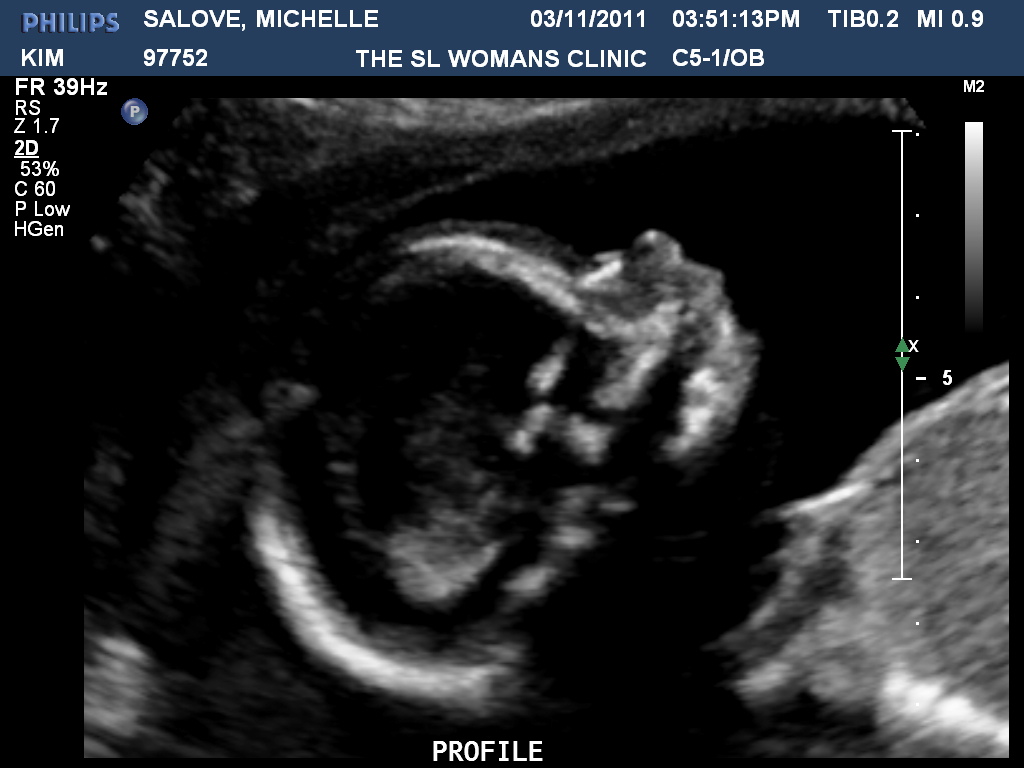

Baby had the hiccups during the visit so that was fun to see. :)

Can't wait to kiss that little button of a nose!

"I wanna rock! ROCK!!"